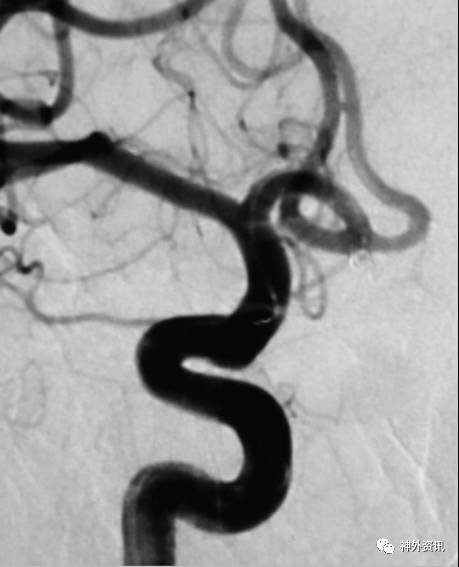

S行塑形

动脉瘤指向与载瘤动脉走向弧度相反(通常A1和M1弓背向上)

(1)指向上方的前交通动脉瘤

(2)指向上方的大脑中分叉动脉瘤

(3)指向上方的颈内动脉终末动脉瘤

(4)指向上方的颈内动脉眼动脉段或床突上段动脉瘤